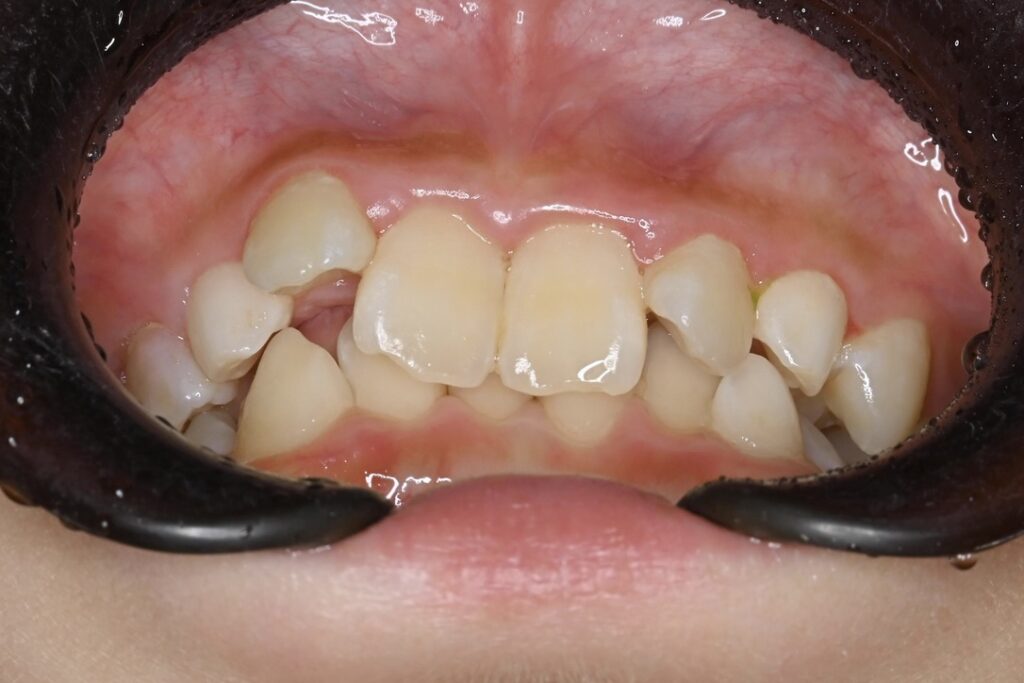

BEFORE

主訴 通っている歯医者で矯正した方がいいと言われて気になっている。下の前歯がでこぼこしている。

診断名・主な症状 下顎前歯の叢生を伴う過蓋咬合

年齢 7歳

治療内容 上下の歯並びの幅を拡げつつ、前歯の関係を改善しました。

使用装置 急速拡大装置

リンガルアーチ

機能的矯正装置(マイオブレース)

抜歯部位 抜歯なし

治療期間 2年 + 後戻り止め期間(3年 )

通院回数 20回

費用 50万円程度(税別)  29331

リスク・副作用 痛み、歯肉退縮、歯根吸収、抜歯に伴う出血や腫れが生じることがあります。